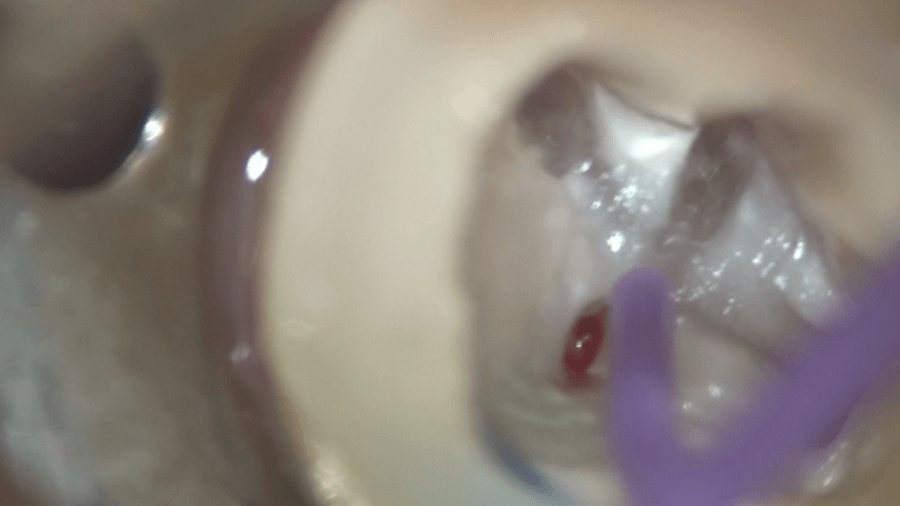

4つの根管の入り口、専門用語で根管口を広げることができました。次回、根管の長さをはかり、大きくし、根の最終的な処置だある根管充填を行い、根管治療を完了させる予定です。

この行程、実は根管治療の中でも、もっとも重要なポイントの一つと言われています。入り口を的確に開けることにより、根管の処置をやりやすくできるのは、想像できるかと思います。